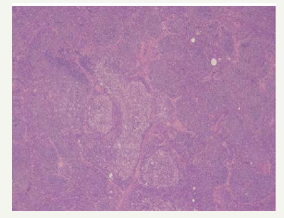

The majority of instances of composite lymphomas may elucidate binary forms of Non-Hodgkin’s Lymphoma, predominantly comprising of mixed small and large cell lymphoma. The infrequent combination of a Hodgkin’s lymphoma and Non- Hodgkin’ Lymphoma confined to a singular lymph node may be considered as an amalgamation of disparate clinico-pathological entities [4-6] Composite lymphoma generally manifests as two divergent morphological lesions arising in a solitary lymph node. The histological variants may belong to an identical lineage of a B cell lymphoma, a subtype of a T cell lymphoma or an exceptional collocation of a B and a T lymphocyte tumour. Additionally, a composite lymphoma may signify a dual occurrence of Hodgkin’s lymphoma and Non-Hodgkin’s lymphoma in a singular lymph node (Figure 3).

Figure 3:CL: a melanoma admixed with small lymphocytic lymphoma [15].